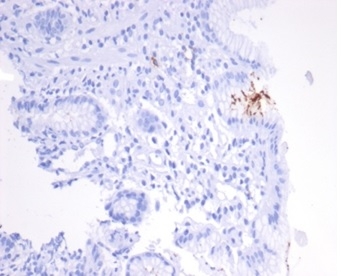

Immunohistochemistry (IHC)

1-2ug/ml

30 min at RT. Staining of formalin-fixed tissues requires heating tissue sections in 10mM Tris with 1mM EDTA, pH 9.0, for 45 min at 95°C followed by cooling at RT for 20 minutes

The spiral shaped bacteriumHelicobacter pyloriis strongly associated with inflammation of the stomach and is also implicated in the development of gastric malignancy.H. pyloriis known to cause peptic ulcers and chronic gastritis in human. It is associated with duodenal ulcers and may be involved in development of adenocarcinoma and low-grade lymphoma of mucosa associated lymphoid tissue in the stomach.This antibody stains the individual H. pylori bacterium when it presents on the surface of the epithelium or in the cytoplasm of the epithelial cells in biopsy tissue sections from the antrum and body of the stomach.

Helicobacter pylori infected stomach biopsy